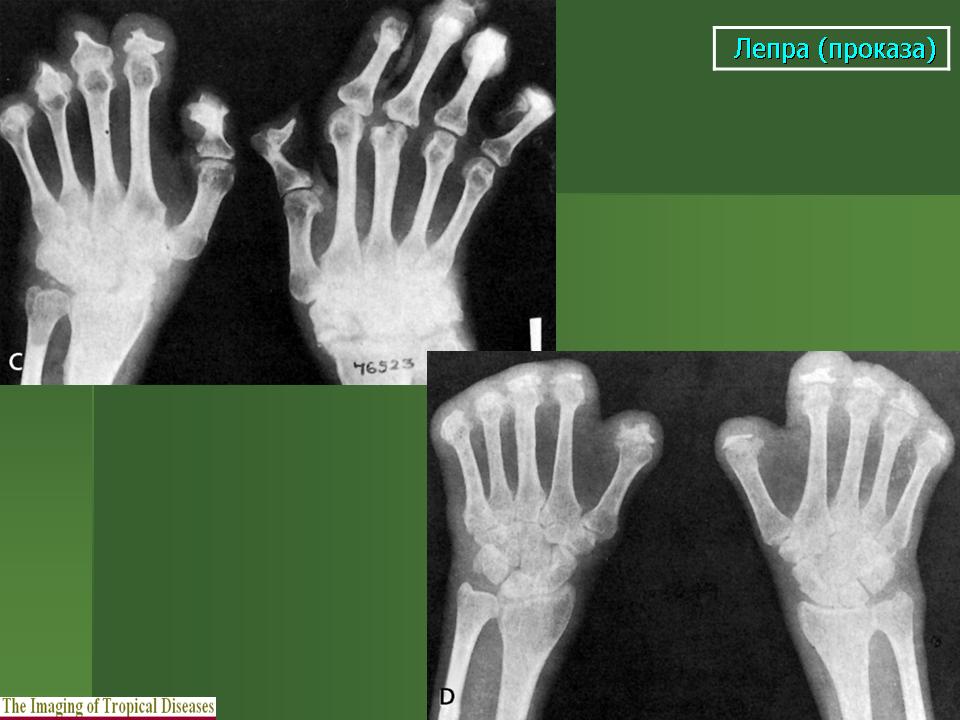

В третьей группе костных изменений при проказе (рис. 217, 218) сочетаются элементы первых двух групп, т. е. специфические и неспецифические. Из особенностей проказы вытекает крайняя неповторяемость частных проявлений в каждом индивидуальном случае заболевания.

Что касается нервной формы проказы (рис. 216), то наиболее ранним, постоянным и общим рентгенологическим ее проявлением служит остеопороз. IK остеопорозу рано присоединяются явления остеолиза. Иконография (т. е. описание картины) остеолиза дается различными авторами в традиционном для лепрологии стиле в чрезвычайно тонких и кропотливых внешне описательных образах. Здесь преобладают сравнения с общеизвестными предметами, как, например, отточенными кончиками карандаша, шахматными пешками и другими фигурами, кнопками, пуговицами для воротника, запонками, тающими свечами, обсосанными леденцами, столбиками, иглами и т. д. Существенно то, что налицо частичное или полное рассасывание и исчезновение костных элементов без их замещения другой тканью и без продуктивной репаративной реакции. Характерно истончение и укорочение костей, в первую очередь ногтевых фаланг. Рассасывание ногтевой фаланги начинается с ее ногтевого отростка. Структура бугорка становится крупнопористой, ноздреватой. Затем срезается дистальный или боковой край, развивается плоская или вогнутая узура, постепенно увеличивающаяся, а затем и весь ногтевой отросток сходит на нет; обнажается шейка. Основание фаланги рассасывается с одного края или с обеих сторон, иногда и целиком. В дальнейшем без каких-нибудь клинических признаков очередь доходит до фаланг средних и основных, а также пястных и плюсневых костей, с переходом на запястье и предплюсну, порой до полного исчезновения скелета одного, нескольких, многих или всех пальцев.

В локализации этих костных поражений трудно определить какую-нибудь иннервационную закономерность, т. е. связь с тем или иным иннервационным районом, что свойственно всем костным поражениям "а нервнотрофической почве. Если в одних случаях имеется симметричность поражений, то в подавляющем большинстве случаев удивляет именно асимметрия двусторонних поражений. Тяжесть калечения при нервной проказе не находится в прямой связи с длительностью забдлевания.

Здесь также часто наступают нарушения целости костей -- истинные патологические переломы, без периостальной активности, без заживления костной мозолью. Переломы ускоряют рассасывание костей. Их не следует смешивать рентгенологически с костными дефектами на протяжении метафиза или диафиза кости. Иногда исчезновение костной ткани происходит сильнее проксимально, чем дистально, и отдельные костные участки могут "повиснуть" в мягких тканях. Отсюда они отходят, отторгаются наружу наподобие секвестров при костном панариции; трудно сказать, в какой мере здесь играет роль совсем необязательная вторичная инфекция, крайне вялая, если она действительно имеет место. Иногда развиваются истинные неврогенные остеоартропатии - лепрозные остеоартро-патии.

Вместе с тем при нервной лепре наблюдаются также настоящие костные анкилозы. Чаще всего это происходит в области плюсне-пред-плюсневых суставов, а между суставами малых трубчатых костей кистей и стоп анкилозы при проказе не развиваются. Калечения усугубляются еще тягой мышц. Происходит уклонение фаланг в стороны, большие расхождения суставных концов, крайние деформации. Мы наблюдали и лоозеровекие зоны перестройки костей на обычных и особенно необычных местах, с нормальным или извращенным их течением и исходом.